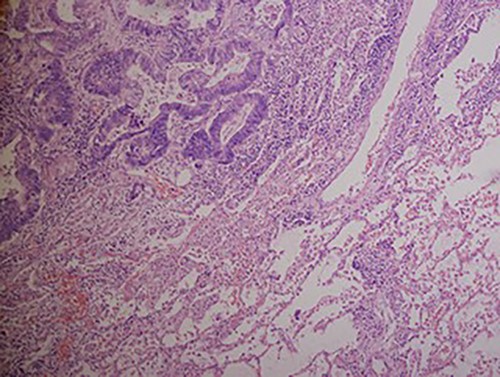

A chest X-ray at the time of admission showed right upper lobe mass (Fig. 1). Tru-Cut biopsy was performed and confirmed the diagnosis of non-small cell carcinoma (Figs 2 and 3). Multiple sections showed two nodules composed of well differentiated adenocarcinoma. The largest one measuring 4 mm from the resection margin, 2.5-cm away from hilar region and 5 mm from the outer surface. Smallest nodule was also composed of well-differentiated adenocarcinoma present 3 mm from the outer surface.

Hematoxylin and eosin stained histopathologic images illustrating lung tissue infiltrated by metastatic adenocarcinoma from colon (hematoxylin–eosin, original magnification ×200).

Low magnification power view of liver tissue with metastatic deposit from colon adenocarcinoma. (hematoxylin–eosin original magnification ×100).